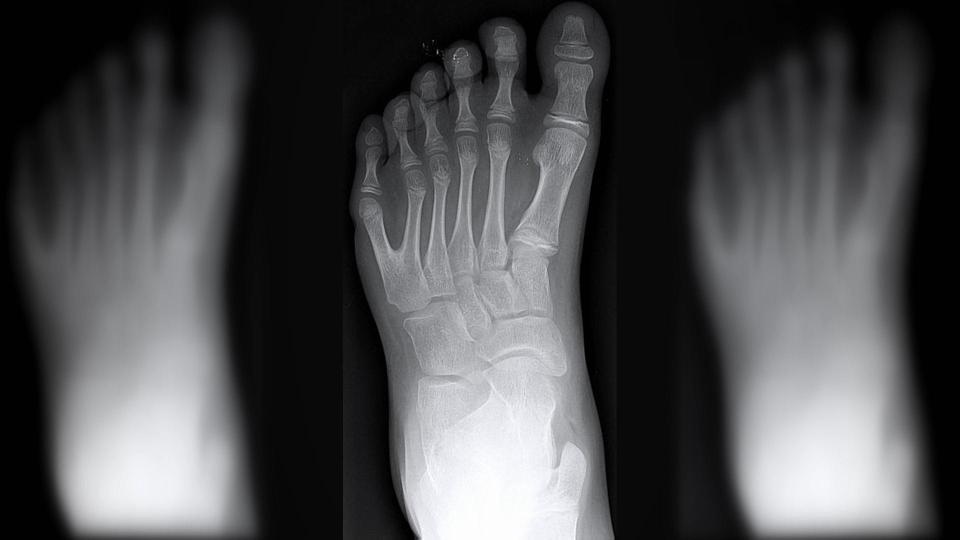

Người đàn ông cho biết tình trạng của gia đình mình là do chứng polydactyly (dị tật thừa ngón) và chỉ xảy đến với tỷ lệ 1/1.000 đứa trẻ. Dù vậy, khả năng xảy ra tình trạng này trong dòng họ De Silva là khá cao. Ví dụ như Alessandro, do kết hôn với một người phụ nữ bình thường nên con trai Vinicius của họ có 50% cơ hội sở hữu gien 6 ngón trên một bàn tay.

“Chúng tôi phát hiện Vinicius là một cậu bé vào tuần thai thứ 13 và từ lúc đó, chúng tôi đã hy vọng rằng con sẽ có 6 ngón trên một bàn. Quả thật khi ra đời, thằng bé đã có được điều đó, các ngón tay của nó cũng hoạt động bình thường”, bà mẹ Katia chia sẻ.

Con trai đầu lòng của Alessandro là Guillherme cũng có 12 ngón tay, 12 ngón chân ngay từ lúc mới sinh. Cậu bé 7 tuổi rất tự hào về đặc điểm này và còn khẳng định có nhiều ngón tay giúp mình cầm nắm được nhiều thứ hơn. Anh họ của Guillherme là Maria và Joao Assis còn cho rằng 6 ngón tay trên một bàn giúp ích cho việc học piano và làm thủ môn bóng đá rất nhiều.